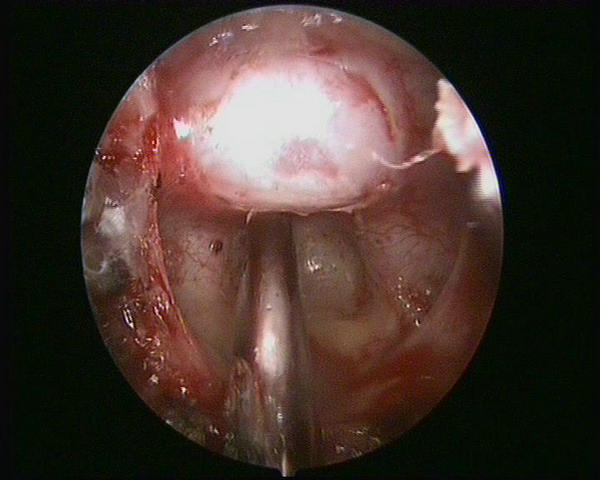

手术非常成功,在切除肿瘤的同时,完好地保护了王女士的视神经、下丘脑、颅底动脉等重要结构。术后第2天,王女士即能下地行走,视力也得到明显改善,视野较术前扩大,头痛乏力的症状也消失了。没有出现其他并发症,一周后即康复出院,复查头颅CT肿瘤切除满意(图5)。

图5